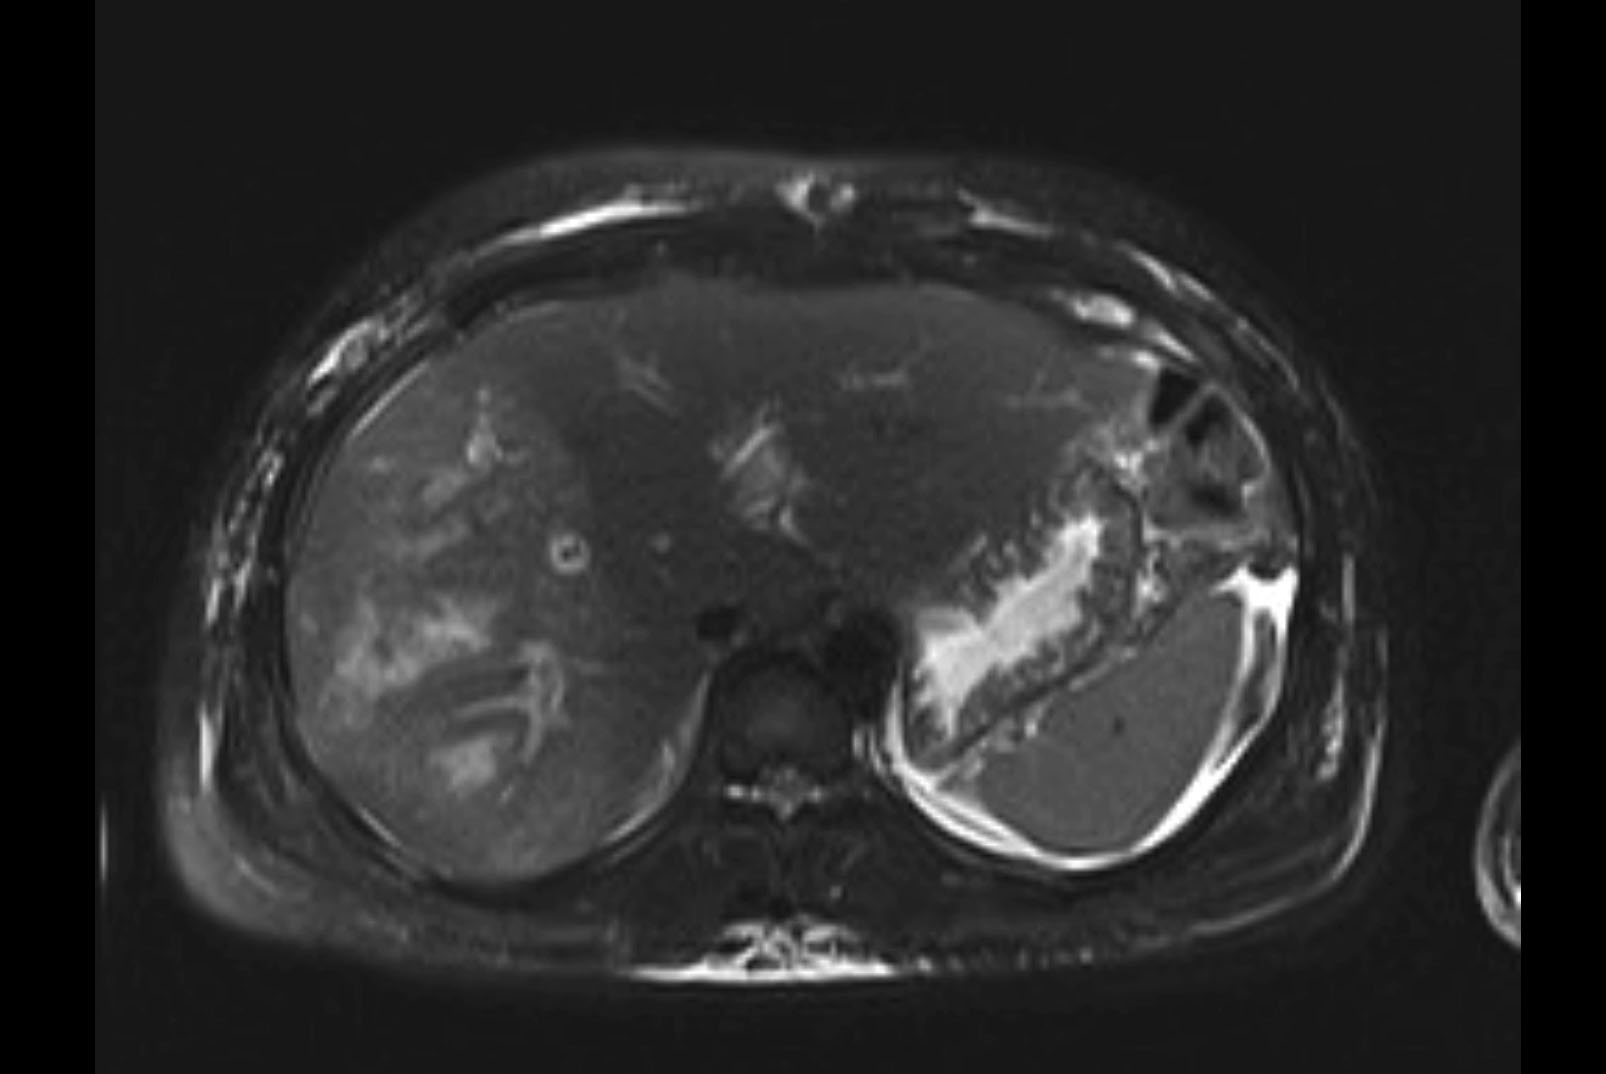

Imaging Analysis

Look through the patient's CT scan to identify any areas of concern for the necessary procedure.

MRI T1

MRI T2

Based on initial findings, which issue(s) would you be most concerned about?